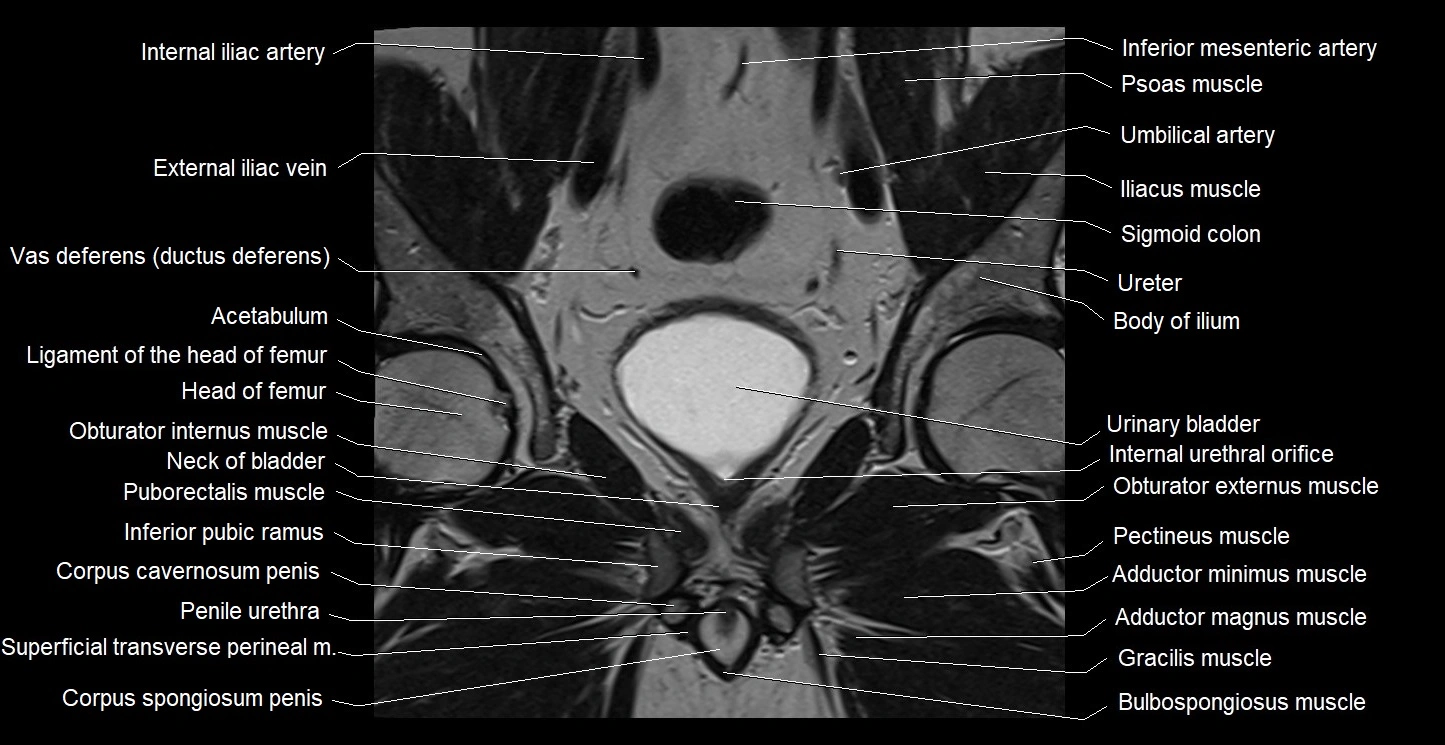

- Acetabulum

- Adductor minimus muscle

- Body of ilium

- Bulbospongiosus muscle (Male)

- Corpus spongiosum

- Crus of penis

- External iliac vein

- Gracilis muscle

- Head of femur

- Inferior pubic ramus

- Internal urethral orifice

- Obturator externus muscle

- Obturator internus muscle

- Pectineus muscle

- Penile urethra

- Puborectalis muscle

- Superficial transverse perineal muscle

- Urinary bladder